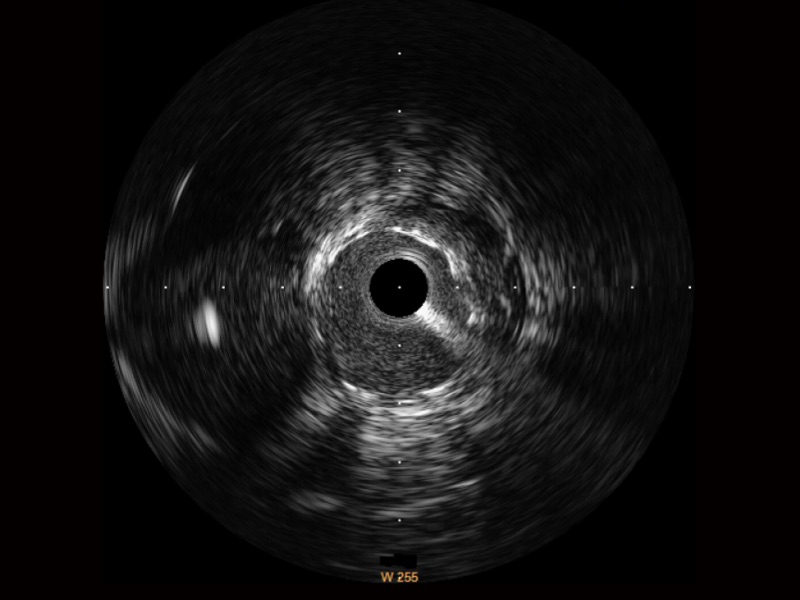

环球UG官网宽频IVUS图像

对比传统IVUS导管成像,环球UG官网宽频IVUS图像的近场支架梁显影更细腻,远场中膜外血管仍清晰可辨,兼顾远中近,兼顾分辨力与穿透深度